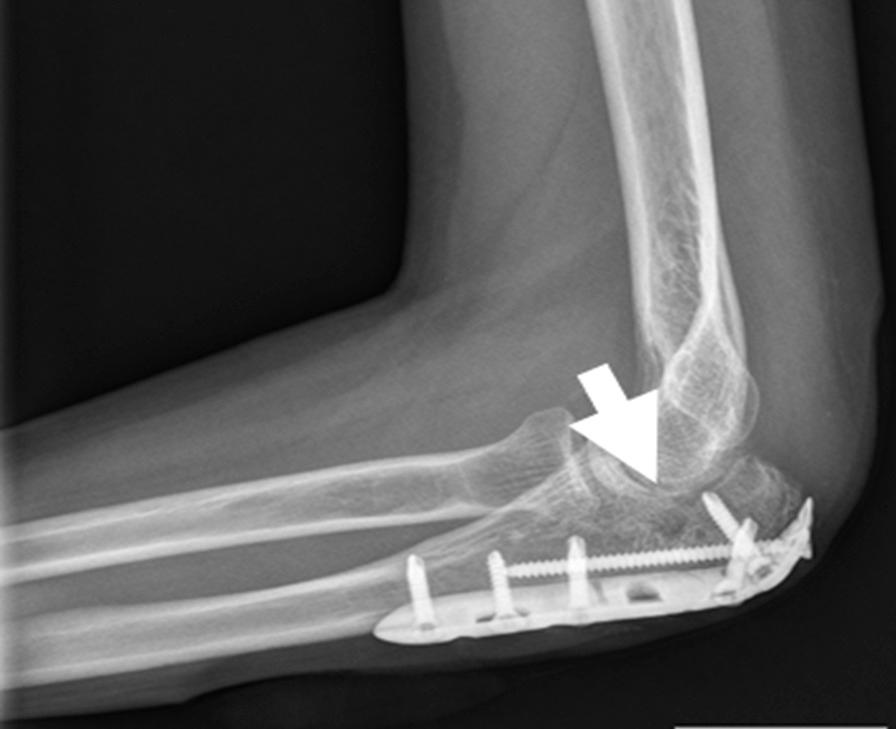

When a fracture goes into or around a joint, it usually damages the cartilage at the ends of bones and other joint tissue. As a result, the affected joints are prone to traumatic arthritis, leading to stiffness. Repairing bone damage, maintaining joint integrity, and avoiding subchondral and metaphyseal defects caused by comminuted fractures is often a great challenge for orthopedic surgeons. Tissue engineering of synthetic bone substitutes has proven beneficial to the attachment and proliferation of bone cells, promoting the formation of mature tissues with sufficient mechanical strength and has become a promising alternative to autograft methods. The purpose of this study is to retrospectively evaluate the clinical outcome and efficacy of a novel synthetic, highly biocompatible, and fully resorbable Ca/P/S-based bone substitute based on medical image findings.

A synthetic, inorganic and highly porous Ca/P/S-based bone-substituting material (Ezechbone® Granule, CBS-400) has been developed by National Cheng-Kung University. We collected fourteen cases of complex intra- and peri-articular fractures with Ezechbone® Granule bone grafting between 2019/11 and 2021/11. We studied the evidence of bone healing by reviewing, interpreting and analyzing the medical image recordings.

RESULTS

In the present study, CBS-400 was observed to quickly integrate into surrounding bone within three weeks after grafting during the initial callus formation of the early stage of repair. All of these cases healed entirely within three months. In addition, the patient may return to daily life function after 3.5 months of follow-up and rehabilitation treatment.

Ezechbone® Granule CBS-400 was proved capable of promoting bone healing and early rehabilitation to prevent soft tissue adhesions and joint contractures. Moreover, it has a high potential for avoiding ectopic bone formation or abnormal synostosis.